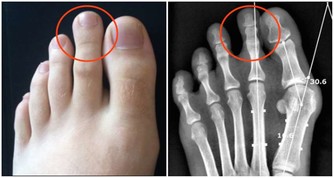

甲狀旁腺被拿掉了,必然影響全身鈣質的吸收,就要終生補鈣。長期缺鈣對身體的影響是巨大的,甲狀旁腺的功能是強大的,損失了它,代價是巨大的。短時間的血鈣低身體就會發麻,抽搐,長期的缺鈣會導致骨密度降低,引起骨質疏鬆,你就是那個一碰就碎的玻璃人。輕輕的一個跟頭,就能斷了胳膊腿。

第一次手術我的左側甲狀旁腺就被拿掉了,但是我不知道,醫生也沒有醫囑。在那個年代也沒有補鈣的概念的。我記得大肆廣告補鈣是在95、96年,我87年做的手術時可沒人給我說過這個事情。幸好我右側的甲狀旁腺保留了,它的功能也有了代償。所以沒有發生過抽搐等現象。但是其實身體是出於缺鈣的症狀的,我的腳趾甲就沒長起來,只有兩個大腳趾有指甲。

萬幸我的個子是長起來了,165cm,算是中等個了。由於無知,上大學時偷偷停了半年的藥,我就是不想終生服藥,想看看停藥有什麼不行的。半年後,甲減的症狀越來越明顯了,出現了思維跟不上的情況,明顯反應遲鈍。更壞的結果很快就來了,在一次體育跳遠課上輕輕的一跳,就跳成了左腿脛骨粉碎性骨折,打了一個月石膏。後來經過一年的康復鍛煉,腿才又恢復了。我從骨折後有開始恢復服甲狀腺素片了。甲狀腺癌復發有可能是從那時開始的。

在去年的第二次手術,做右側甲狀腺摘除時就把甲狀旁腺也摘除了。這下我的身體就一點甲狀旁腺都沒有了。它的反應非常明顯,而且迅速。手術當晚就因血鈣的迅速流失,腰椎疼了一晚上,直到第二天早上醫生查房後,給我靜脈注射了葡萄糖酸鈣,才止住了疼。

別人一輩子的針都被我紮了。但是沒完,醫生還讓我今後一定定期監測血鈣的含量。同時,每年應該做一次骨密度的片子,看看骨頭里鈣沉積的情況。

如果你也做了甲狀腺癌清掃術,就開始終生補鈣吧,定期監測血鈣含量,別把自己變成個玻璃人。還有一些個別的手術後遺症就屬於手術事故了。那就另當別論了。